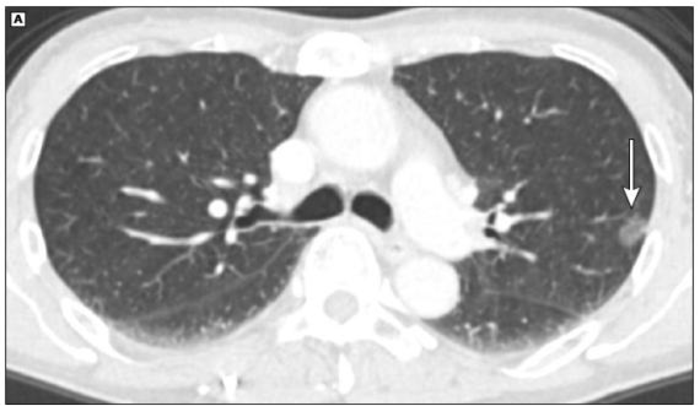

二、我可以用胸片而不是低剂量CT扫描进行筛查吗?

目前肺癌筛查的方法是低剂量的薄层CT平扫,而不是胸片。想象一下大海捞针的难度,就类似于在胸片中找一个很小的肺结节。而CT可以整个肺部分成很多细小的部分,自然更容易找到。

肺部CT(看局部)